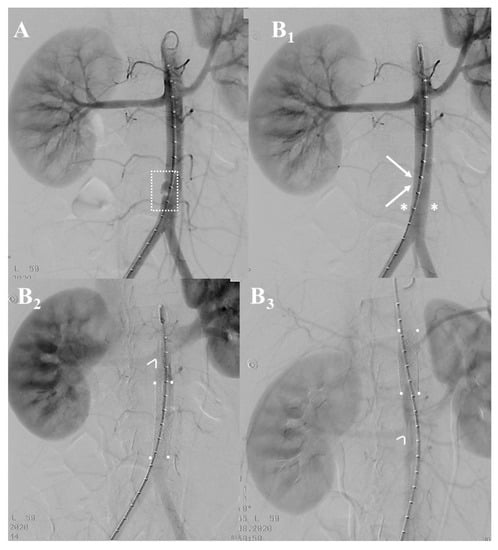

3.2. Institutional Case Report #2—Intra-Abdominal Injury and Endovascular Treatment